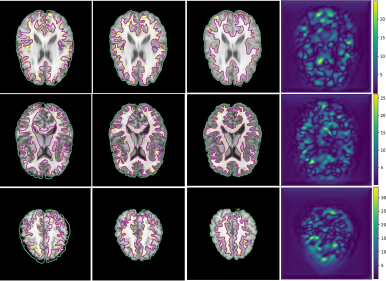

In Fig. 3 Conv2Warp without () regularization and with () regularization are shown in 4th and 5th columns respectively and their corresponding DVF magnitudes in 6th and 7th columns, respectively. It can be observed that the unconstrained loss function results in some unrealistic deformations (red rectangular regions in 4th column) while a more realistic deformations are visible for the constrained loss proposed in Conv2Warp (5th column). A smooth deformation can be seen in the magnitude image of the DVF (7th column). Colour overlay images show a large improvement in the alignment of source images with the target images (3rd column) with Conv2Warp method (5th column). Fig. 4 shows the results on T1 MRI test datasets which were first rigidly aligned to MNIspace and then co-registered using Conv2Warp. It can be observed that Conv2Warp handles different magnitudes of non-linear deformations.